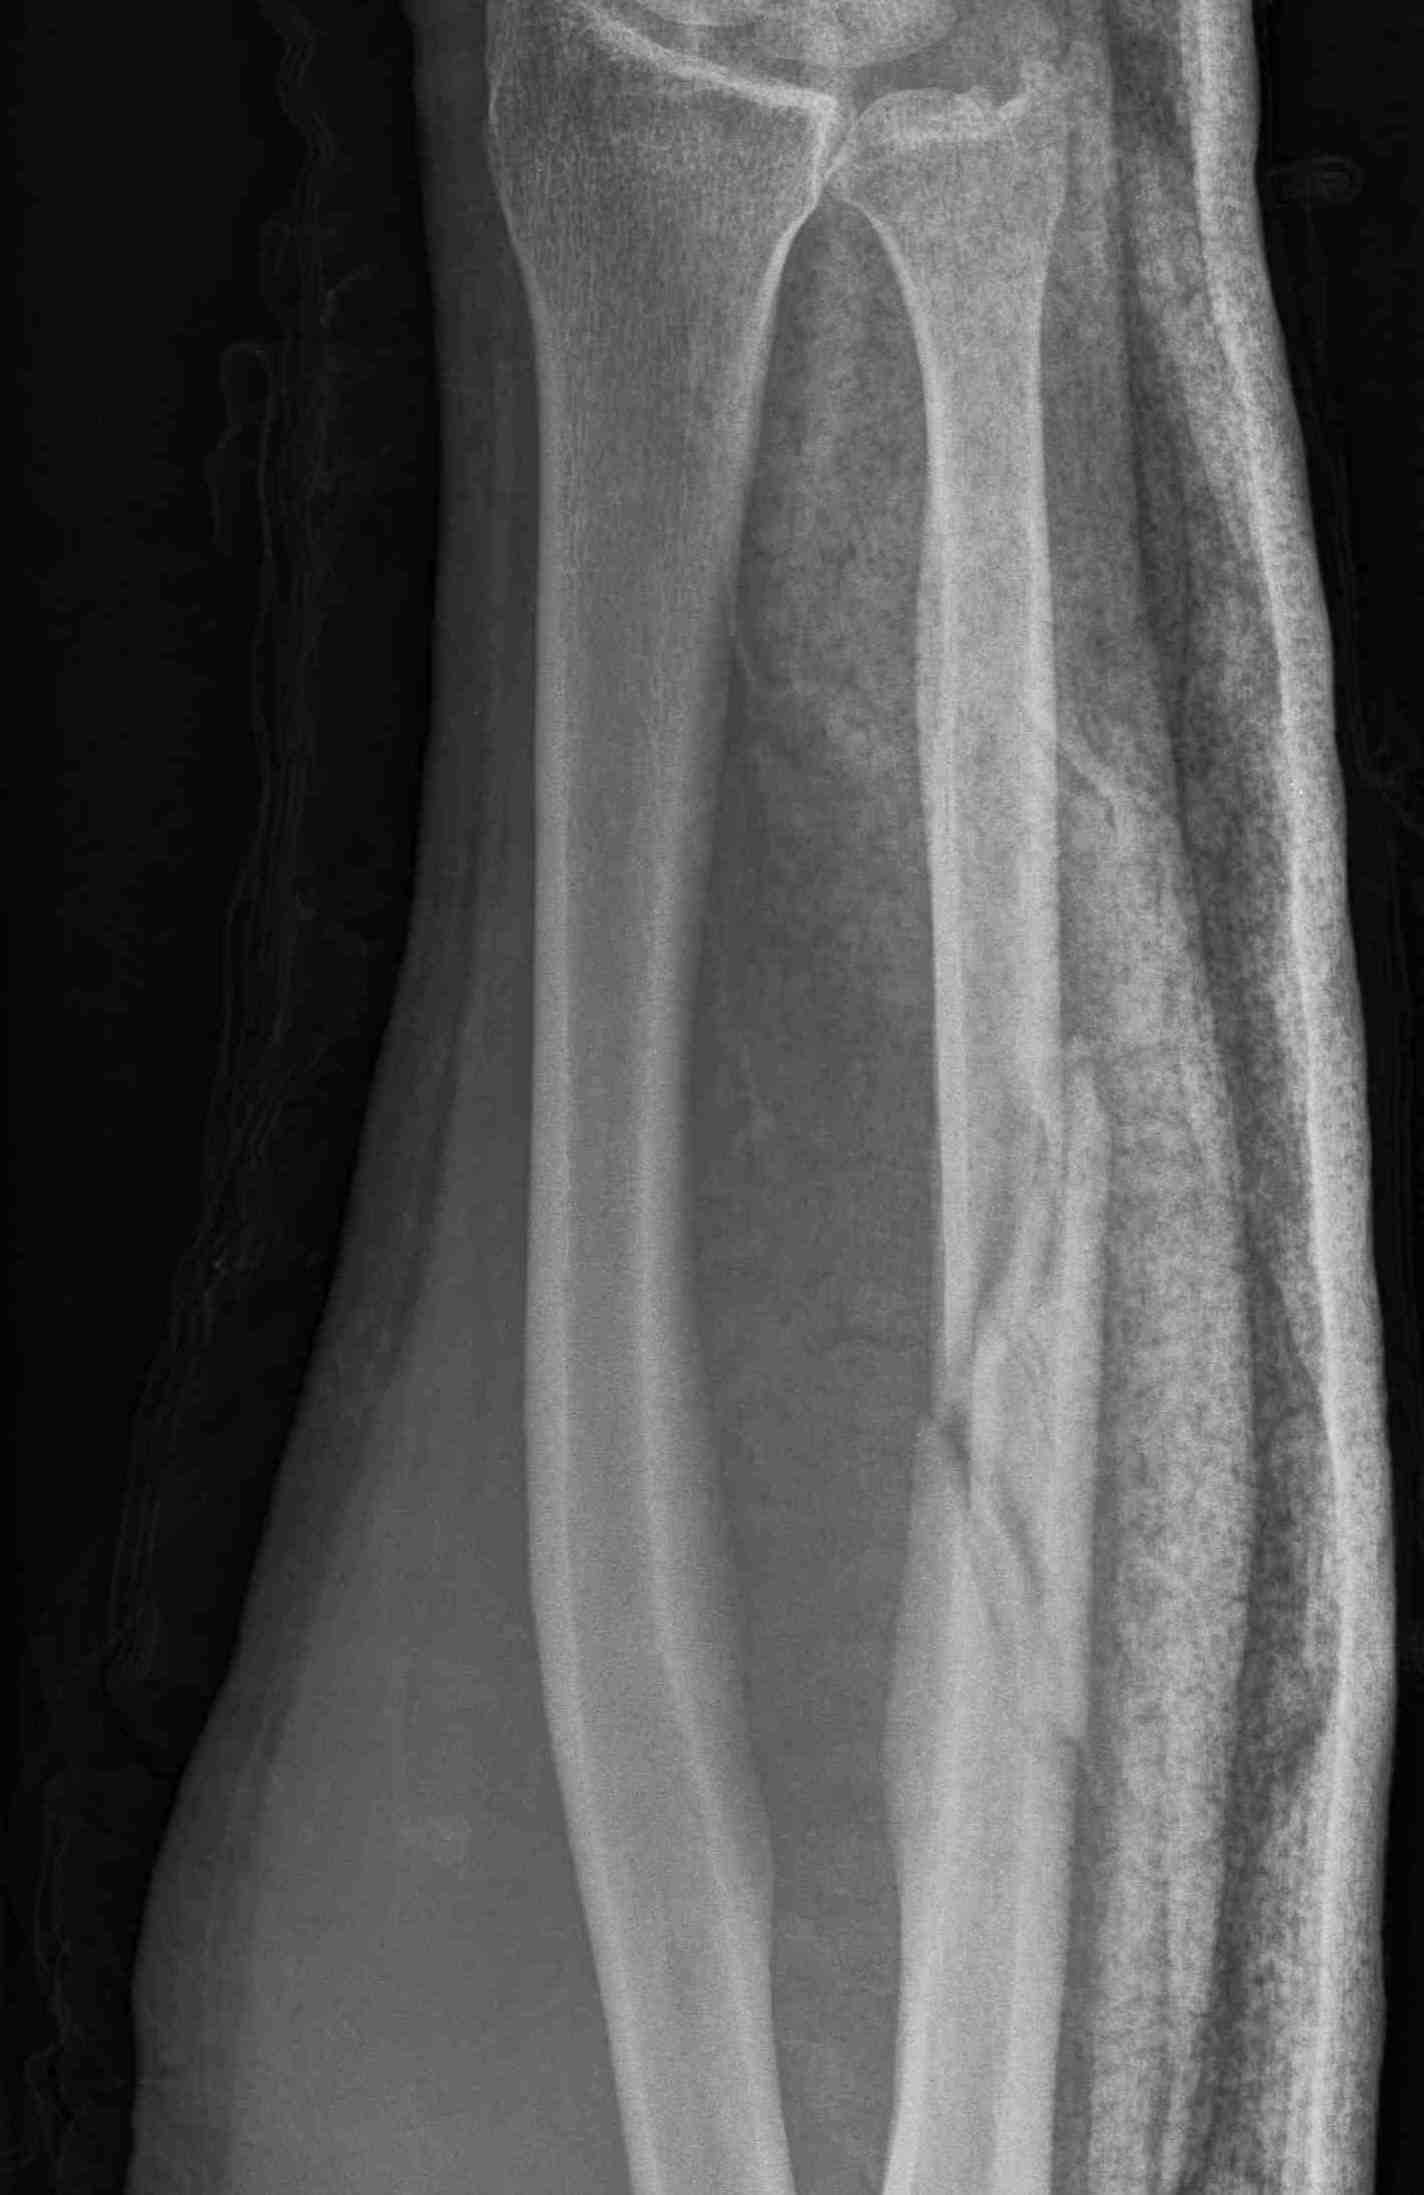

Complications

Ulna nonunion after plating